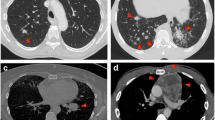

All the specimens were analysed by two pathologists (JA and VdM) who were blinded to patient clinical, imaging and pathological data. The sample size, tumour content, tumour type and histological RFA-induced coagulative necrosis were evaluated with haematoxylin–eosin–saffron (HES) staining (Fig. 2). Post-RF alterations were characterized according to the percentage of coagulation necrosis of the sample (mild, less than 33 %; moderate, at least 33 % and less than 66 %; and intense, at least 66 %).

Representative histological aspects after RFA (haematoxylin–eosin–saffron staining). Arrows indicate identifiable tumour glands within a fibrous stroma (adenocarcinoma) with mild (a) or moderate (b) tissue coagulation artefacts. In one case (c), important coagulation necrosis did not allow any histological diagnosis